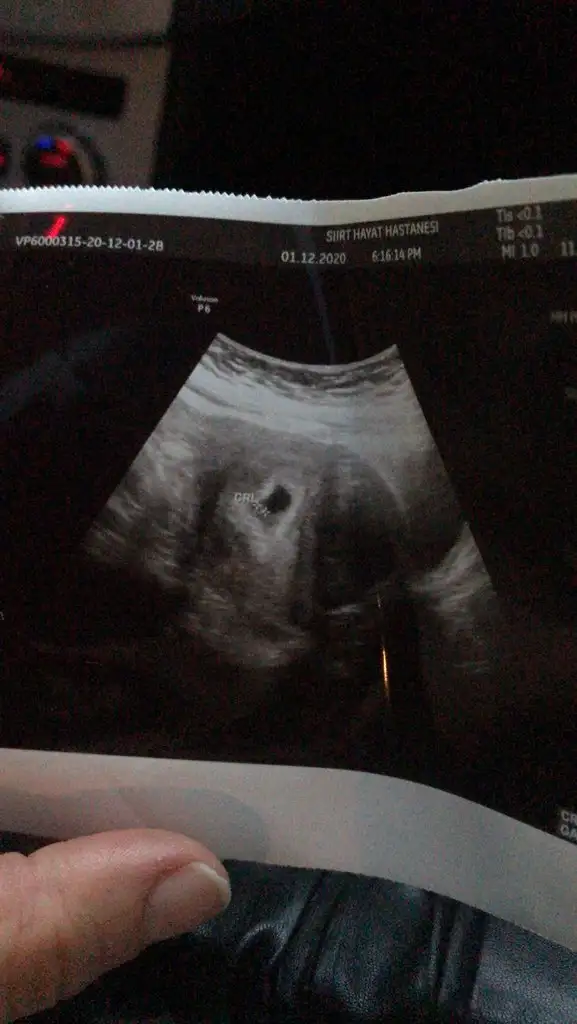

• WhatsApp Image 2021-02-13 at 12.55.22.webp

WhatsApp Image 2021-02-13 at 12.55.22.webp

30,6 KB · Görüntüleme: 84